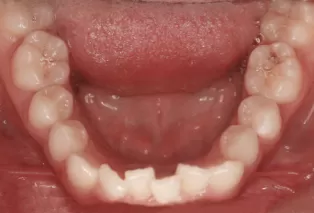

Intraoral photos